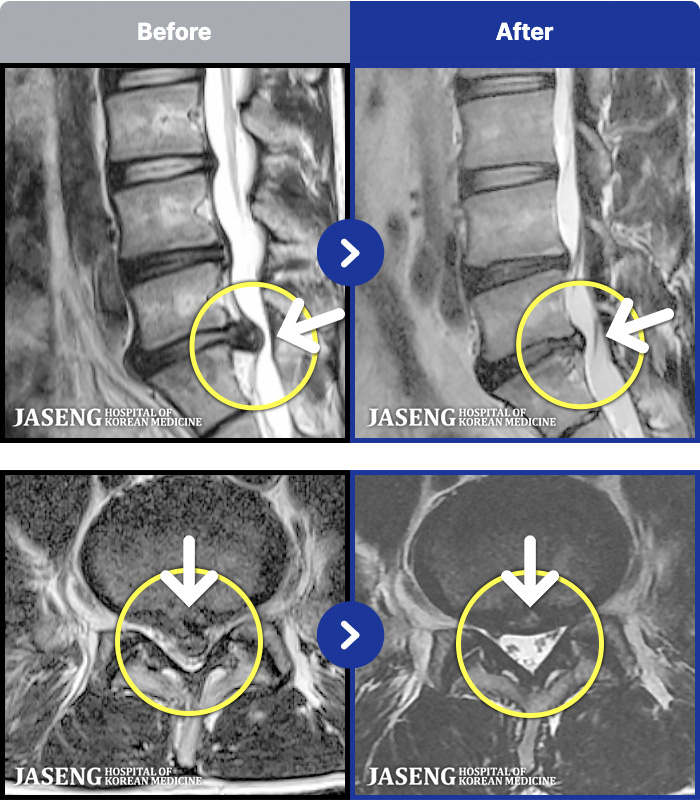

MRI ġ

MRI ũ ʸ Ȯϼ.